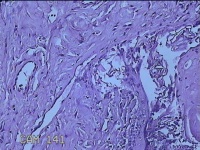

性别

男

年龄

45岁

临床诊断

皮下结节

一般病史

发现左侧一结节,伴局部瘙痒不适1年。

标本名称

左侧结节

大体所见

灰白暗红色带皮肤样结节0.8x0.7x0.3cm一个,表面糜烂,切开结节呈实性,切面灰白粉红色,质软。

感觉像表皮样囊肿?